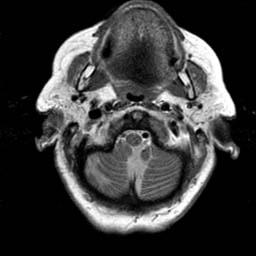

To demonstrate the effectiveness and efficiency of the proposed image fusion method , we conduct a set of comparative experiments on three image datasets. The first is composed by 8 pairs of multi-modal medical images and the second one contains 15 pairs of multi-focus gray or color natural images. These two datasets are often used in many related papers and some examples are shown in Figure 3(a) and Figure 3(b). The third one is a new multi-focus cervical cell image dataset collected by ourselves, which consists of 15 groups of color images and each group contains a series of multi-focus cervix cell images with size of or , etc. Some source examples are shown in Figure 3(c). Our source code implemented in C++ along with the new multi-focus cervical cell image dataset is available online.

We first evaluate the performance of the proposed method under varying total number of octaves and number of layers sampled per octave. The fused images of a pair of multi-modal medical images with different and are shown in Figure 4. In this example, on the one hand, when only 1 or 2 octaves are involved in constructing the DoG pyramid, the fused images fail to keep the integrity information of large size objects (e.g. eyeballs), while by increasing the value of , the integrity information of eyeballs is preserved. On the other hand, although not as significant as the increase of octave numbers , the fused image can contain more details by the increase of layer numbers . The corresponding objective quality metrics are shown in Figure 5. As shown in Figure 5(a), most of the metric values are improved as the number of octaves increases with the fixed layer numbers 3 in the global tendency and each of them tends to be stable when the number of octaves is 5. To get a relatively good quality from Figure 5(b), we can notice that some of the metric values can get a good performance when the number of layers is 3, such as the MI, SSIM, QI and VIF, though there are only a little change of all the metric values by increasing the number of layers with the fixed octave numbers 5. Because it will result in more computation burden with the increase of the value and , and for different kinds of source images, there are different performance with the diverse parameter settings. To get a trade-off between them in our experiments, we set for the multi-modal dataset, for the natural datasets and for the multi-focus cell dataset, respectively.

Figure 6 shows the fused images obtained by different methods with the multi-modal source images shown in Figure 3(a). As shown in these figures, the proposed method can produce images which preserve the complementary information of different source images well. Moreover, due to the scale-invariant structure saliency selection, our method can keep the integrity information of large size objects and the visual details simultaneously. Although the fused image generated by other methods can also capture the details to some extent, all of them fail to keep the integrity information of large size objects such as the eyeballs. Furthermore, from Figure 6(k)-6(t), the DTCWT, GFF, IM and NSCT methods may decrease the brightness and contrast while the proposed method can preserve these features and details without producing visible artifacts and brightness distortions.